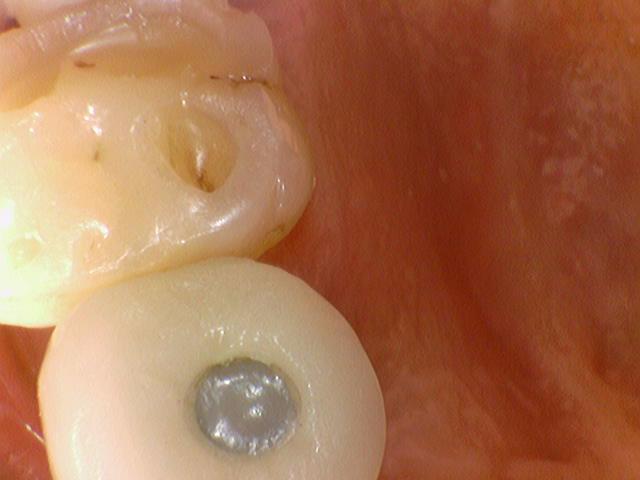

![[서울역/광화문] 오래된 크라운에 음식물이 많이 껴요 →해결방법은? 관련 이미지 1](https://pub-9f2bb3498faf4d1d8714b41df24753e3.r2.dev/content/clinics/archive/rseeanjxfu/naver_blog/yonseiyegam/assets/by_hash/301bf07d03d479cb1ba0988d6c4c9b3464b2447f18c06587b2c27c9986edb33d.jpg)

왼쪽(깨진 임플란트크라운과 치아 사이에 빈 공간이 있어서 음식물이 낌) / 오른쪽(임플란트 크라운 새로 제작)